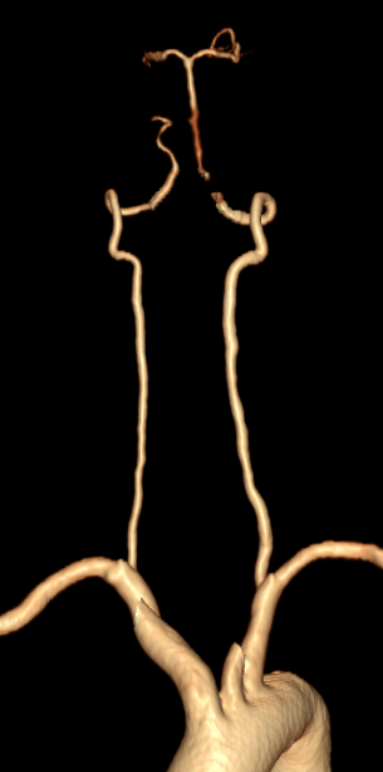

➢头颈部CTA+脑灌注

-

双侧枕叶、丘脑、脑干及双侧小脑半球血流灌注减低,建议MRI检查。

双侧椎动脉V4管腔闭塞,建议DSA检查。

双侧颈内动脉虹吸段钙化斑块,管腔中-重度狭窄;双侧大脑中动脉M1段、大脑后动脉硬化,管腔轻微-轻度狭窄。

双侧大脑前动脉共干。